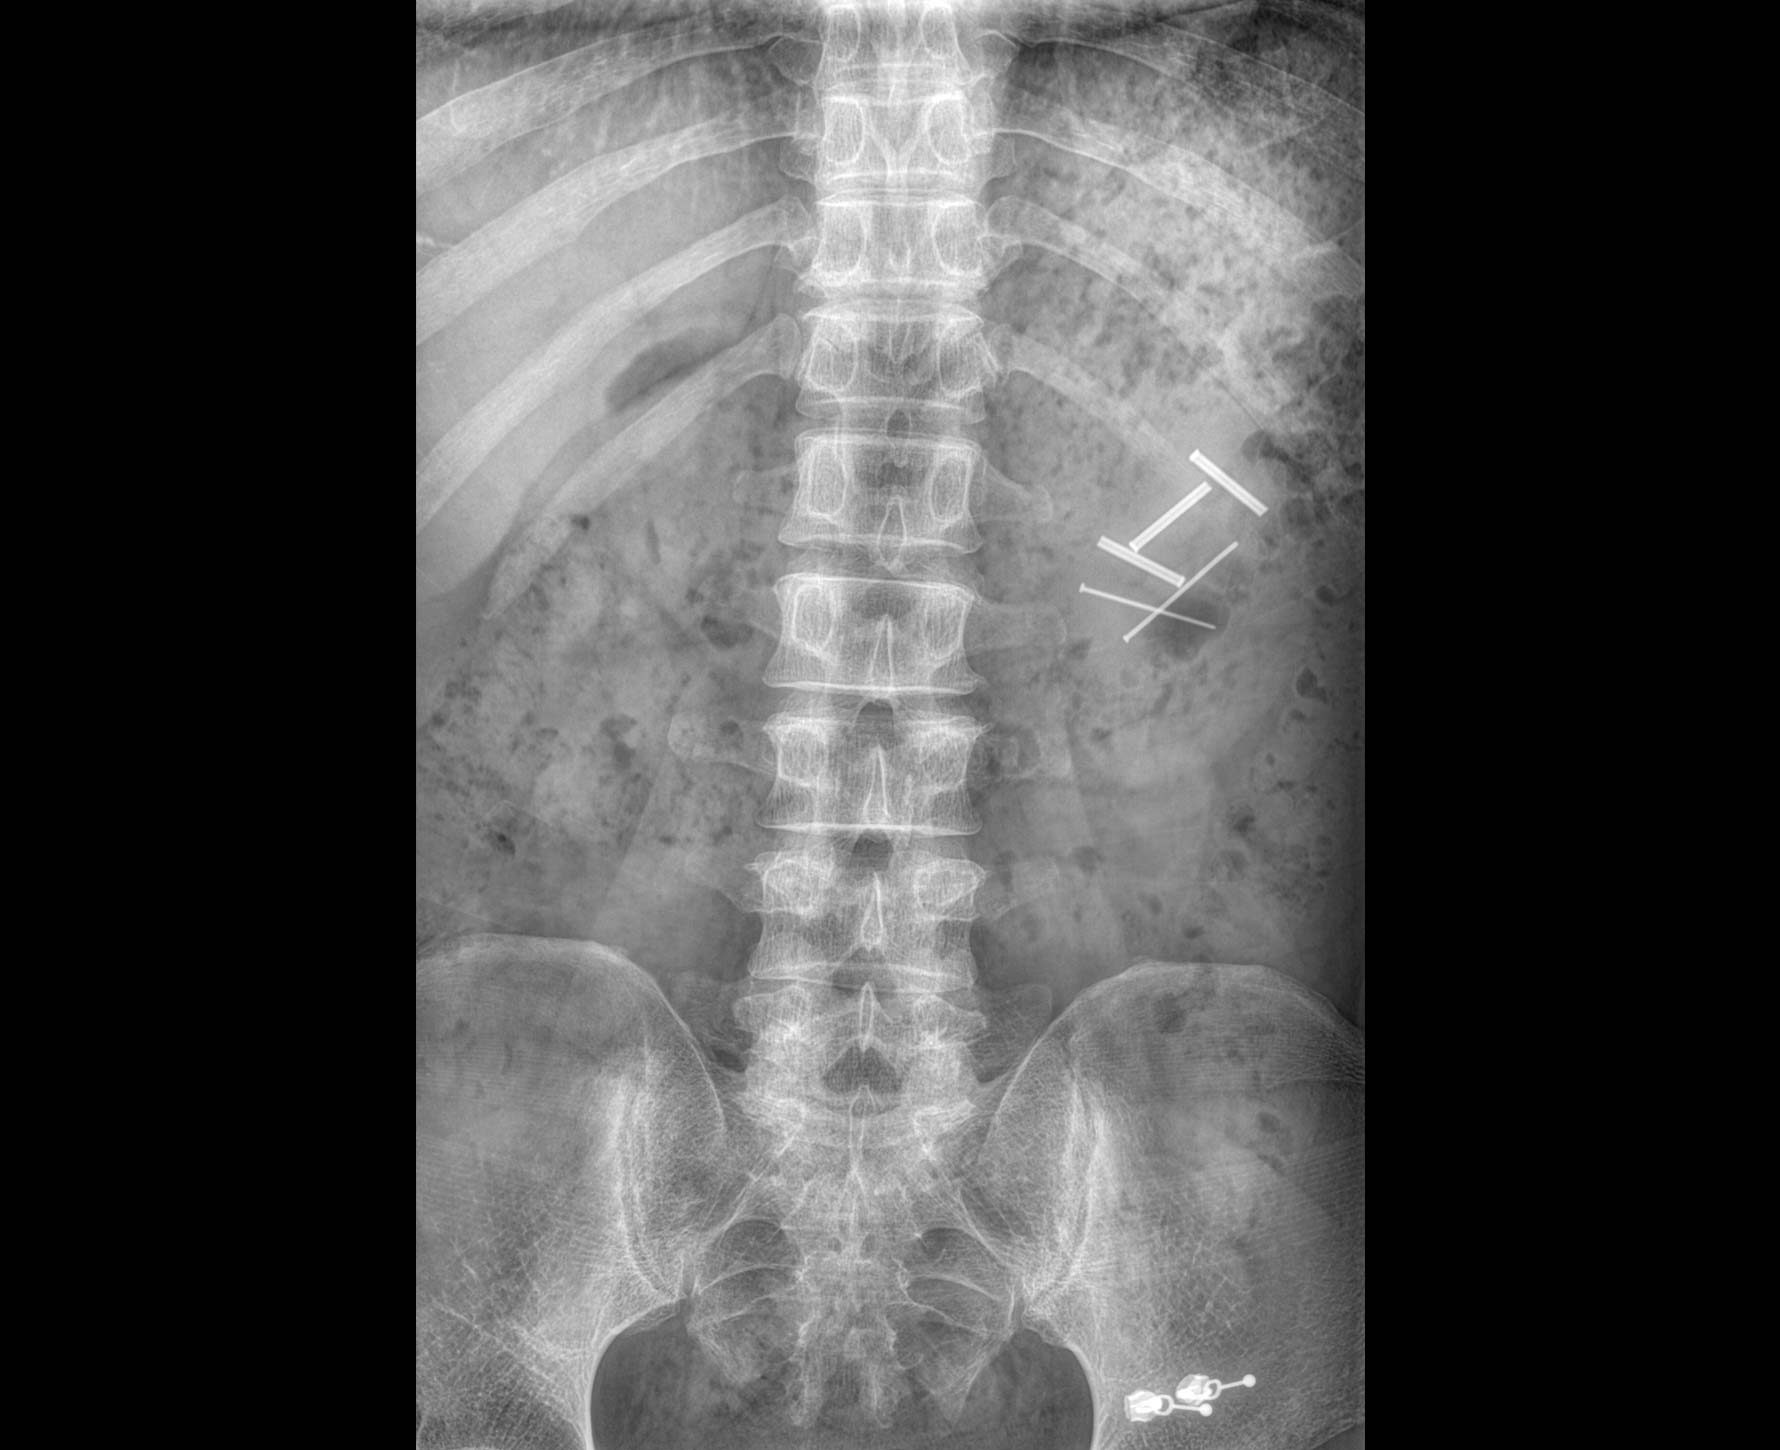

• 拍片

适用于全身各部位摄影

(常规摄影和特殊摄影)

• 标配全身拼接功能

无缝融合处理,保证高质量全景影像。

临床图像